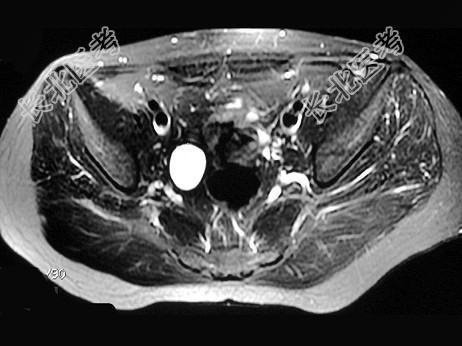

- 多项选择题女,31岁, 右侧腰部胀痛不适,MRI检查如图所示, 下列说法正确的是 ( )

A、右肾重度积水

B、右侧输尿管粗细不均并迂曲扩张

C、右侧输尿管下段呈囊样扩张

D、左肾输尿管未见异常

E、考虑为右侧输尿管囊肿